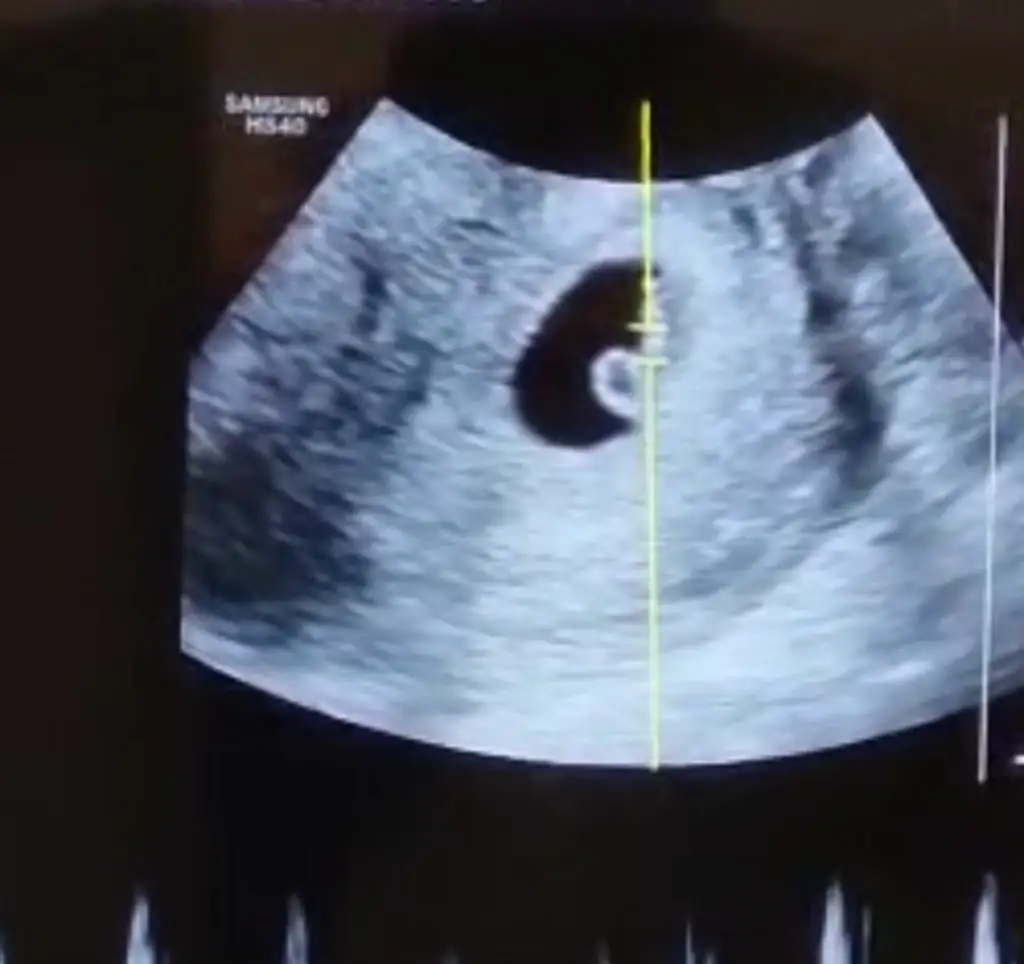

Atmış mıydın ultrason resmi bakalımRamzi , çin takvimi ve bu hesaplama erkek diyor . Ama ben kız hıssedıyorummm

Canımcım sırasıyla attım. Bakalım sen nedıcenAtmış mıydın ultrason resmi bakalım

Kız diyorumCanımcım sırasıyla attım. Bakalım sen nedıcen